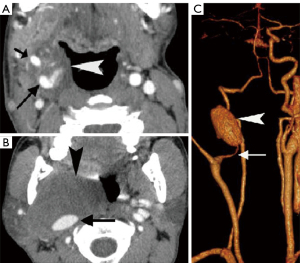

In the past, digital subtraction angiography (DSA) played an important role as a first-line imaging investigation for paragangliomas (26). However, such an invasive method is reserved for those few patients whose diagnosis, after sectional imaging, remains inconclusive, or preoperative embolization. DSA, and sometimes computed tomography angiography (CTA), will show feeding arteries, such as the ascending pharyngeal artery (the artery of the paraganglioma) (Figure 12) and occipital artery (27). DSA also shows intense staining of the tumor and a rapid venous drainage.